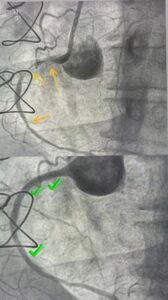

O Hospital Dilson Godinho (HDG), em Montes Claros, deu mais um passo importante na modernização dos cuidados em saúde. Nesta semana, a instituição realizou pela primeira vez um procedimento utilizando o ROTAPRO, a versão mais moderna do rotablator, tecnologia de última geração empregada no tratamento de obstruções coronarianas complexas.

O novo equipamento representa um avanço significativo para a cardiologia intervencionista do Norte de Minas. Ele permite maior precisão, segurança e eficácia nos procedimentos de angioplastia rotacional, especialmente em casos de lesões coronarianas calcificadas, que costumam ser mais difíceis de tratar com os métodos tradicionais.

A intervenção foi conduzida pela Equipe de Hemodinâmica do HDG, formada pelos especialistas Gustavo Albuquerque, Rodrigo Malveira, Gustavo Faria e Reinine Lopes Freitas.

De acordo com o cardiologista Dr. Gustavo Albuquerque, a tecnologia traz ganhos diretos para o paciente e aprimora a capacidade técnica da equipe. “O ROTAPRO nos proporciona controle e estabilidade superiores durante a angioplastia, o que garante um tratamento mais seguro e resultados clínicos mais eficazes”, explica o médico.